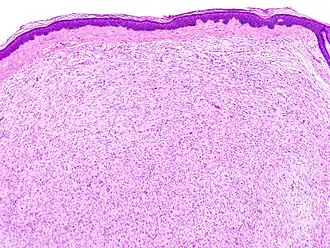

![]() Гистологическое изображение кожной нейрофибромы | |

Общим для структуры нейрофибром является беспорядочное расположение нервных волокон внутри периневрия, где они разделены клетками соединительной ткани. Инкапсулированные нейрофибромы возникают главным образом в крупных нервах. Нерв при этом приобретает на некотором протяжении веретенообразную форму за счёт очагового беспорядочного разрастания нервных волокон, разделённых пучками коллагеновых волокон. В нейрофибромах кожи нервные волокна иногда бывает трудно обнаружить, так как они представлены очень скудно. В инкапсулированной нейрофиброме часто отмечают нарушения лимфообращения, проявляющиеся признаками выраженного отёка. По мере распространения отёка из периневрального пространства на внутреннюю часть нервного ствола усиливается его разволокнение, миелиновые волокна исчезают и заменяются фиброзными тяжами. Дальнейший рост такой нейрофибромы постепенно замедляется и может приостановиться[1].

Диффузная нейрофиброма возникает главным образом в результате поражения мелких нервов кожи. Довольно часто диффузная нейрофиброма состоит из вытянутых леммоцитов (шванновских клеток). В диффузной нейрофиброме иногда обнаруживают пигментные клетки и рецепторы (типа телец Мейснера и Фатера-Пачини). Нейрофибромы, возникающие в симпатическом стволе, могут включать ганглиозные клетки и по микроскопической картине иногда напоминают неинкапсулированную ганглионеврому[1].